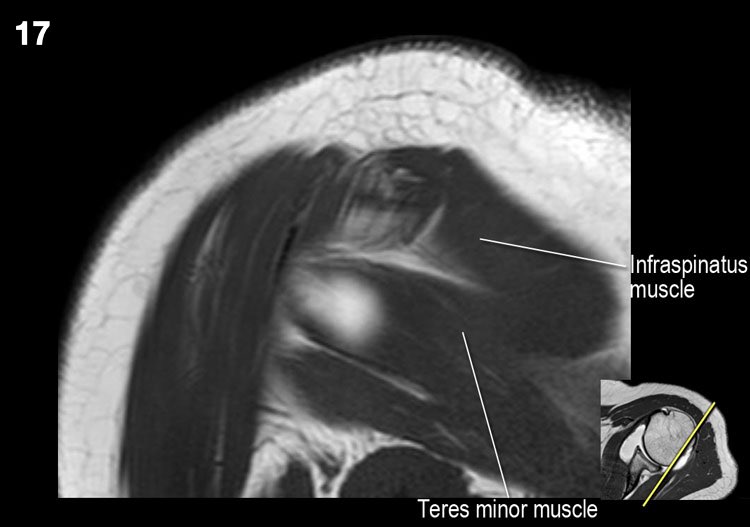

Hình ảnh mặt sau

Hình ảnh thể hiện các cơ và gân của cơ trên gai, cơ dưới gai và cơ tròn bé. Tất cả đều bám vào mấu động lớn.

Các cơ và gân chóp xoay có chức năng ổn định khớp vai trong quá trình vận động.

Nếu không có chóp xoay, chỏm xương cánh tay sẽ trượt lên một phần ra khỏi hõm ổ chảo, làm giảm hiệu quả hoạt động của cơ delta.

Rách lớn chóp xoay có thể khiến chỏm xương cánh tay di chuyển lên trên, dẫn đến hình ảnh chỏm xương cánh tay nằm cao bất thường.